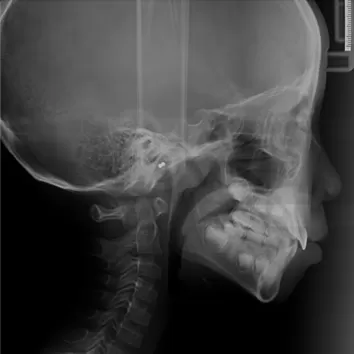

X-rays before treatment

[Panoramic Radiography/Lateral Cephalogram]